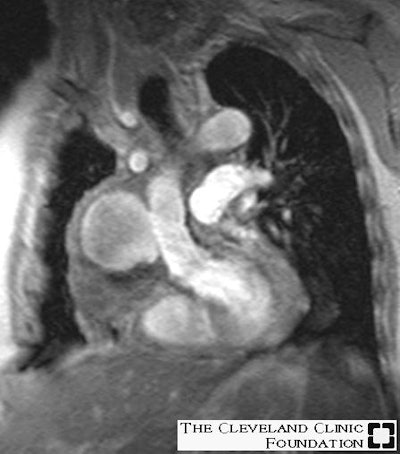

Infectious Aortic Pseudoaneurysm:

Below are images of a pseudoaneurysm at the distal anastamosis of an ascending aortic homograft that occurred secondary to infection. Both images were obtained in a double oblique coronal projection. The first image is a fast spin-echo T2-weighted sequence showing the large pseudoaneurysm that contains a mild amount of thrombus along the periphery, while the second image is a cine gradient-echo demonstrating the wide (3 cm) communication between the pseudoaneurysm and the ascending aorta.